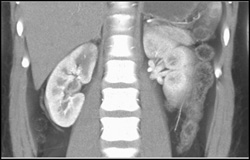

Cystic Renal Cell Carcinoma and Cysts